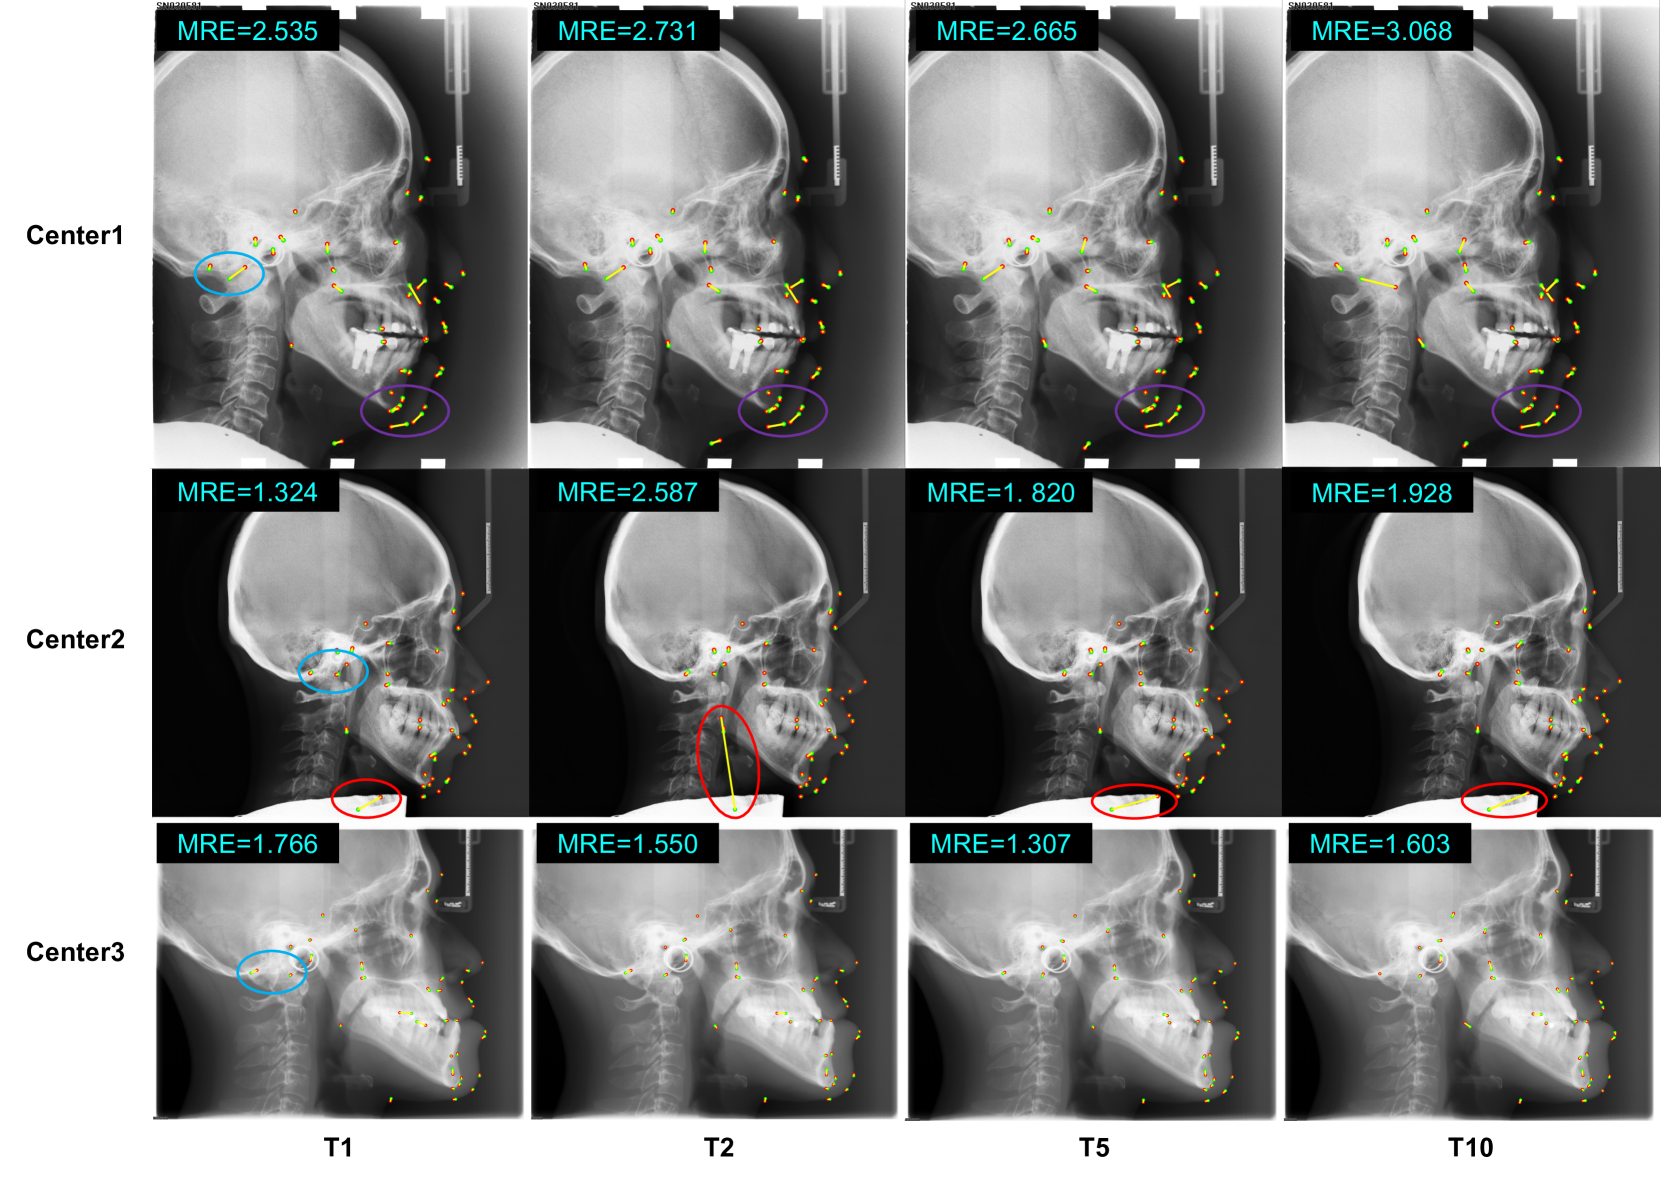

Refer to caption

Figure 8: Landmark visualization results in different medical centers of the different four teams (T1, T2, T5 and T10). The green point and red point denote the ground truth and prediction landmarks, respectively. The yellow line is the line between ground truth landmark and prediction landmark.

Another hypothesis suggests that soft tissue-related landmarks are more difficult to localize than bone-related landmarks due to low contrast in nearby areas [12, 13]. However, upon a thorough analysis of the detection results, we observed no significant differences between the outcomes for soft tissue-related and bone-related landmarks, as demonstrated in Table 6. Furthermore, it is unexpected that soft tissue-related landmarks are easier to detect than bone-related landmarks as the scores relative to this group get the larger MRE and lower SDR@2.0mm. As seen from the comparison of landmarks in the purple and blue areas in Fig. 8, soft tissue-related landmarks are influenced by low contrast, but bone-related landmarks face challenges due to the overlapping nature of skull bones. This complexity makes it difficult to determine definitively which type of landmark is more easily detectable.

Another hypothesis generally accepted in the machine learning community is that heatmap-based landmark detection methods overlook the topological structure between landmarks [31]. As illustrated in the first row of Fig. 8, the relative positions of some predicted landmarks do not conform to the expected anatomical relationships. This may be because the top 10 algorithms are all heatmap-based solutions. During heatmap decoding, each landmark’s heatmap is processed individually without considering the topological connections between landmarks. This oversight leads to inherent errors in the final post-processing stage. Despite the availability of post-processing techniques like DARK [49] that aim to mitigate these issues, such discrepancies remain unavoidable.

In addition, the comparison of the landmarks in the red circle of Fig. 8 reveals that different ranking algorithms fail to execute when landmarks are obstructed, leading to significant location errors. This issue may stem from the CNN-based algorithms excelling at capturing local information but failing in perceiving occluded landmarks [33]. Moreover, the intrinsic shape constraints inherent in heatmap-based methods [31] are absent, resulting in the predicted landmarks appearing at inappropriate locations. However, it is worth pointing out that the algorithm designed by T1 has the smallest error in this case compared to other teams. Therefore, we believe that the detection of occluded landmark points would be solved through more sophisticated design algorithms, such as graph convolution that are good at handling topological structures or a Transformer model that are long-range aware.